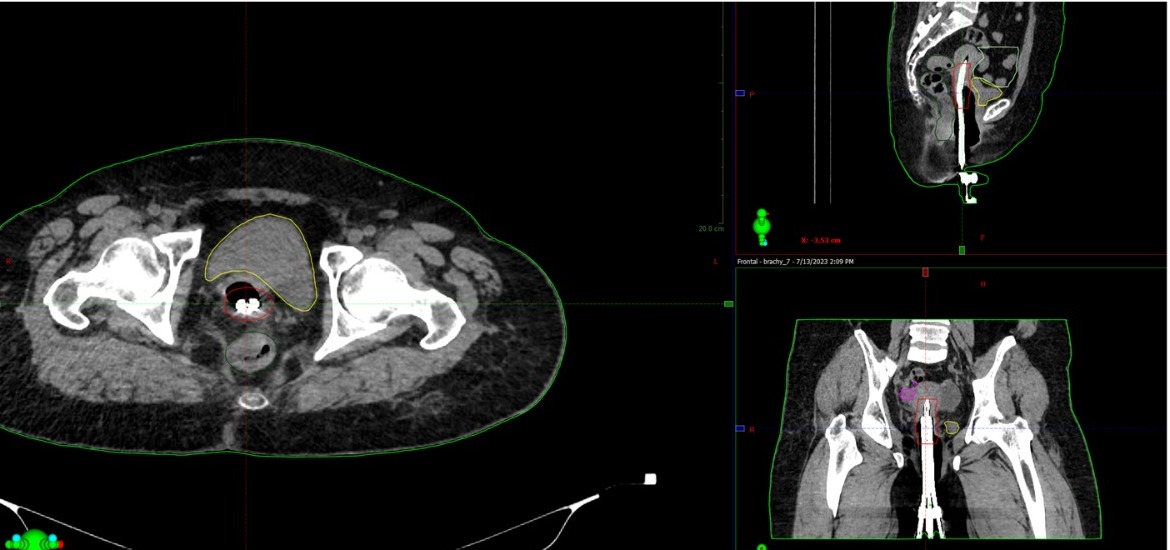

Қатерлі ісікті емдеудің тағы бір тиімді әдісі – сәулелі терапия. Биылғы мамыр айынан бастап батысқазақстандықтардың да бұл емге қолы жетті. Өңірде ядролық медицина орталығы ашылғанын бұдан бұрын сүйіншілеп жазған едік. Содан бері өткен аз уақыт ішінде оралдық мамандар радиологияның соңғы мүмкіндіктерін пайдаланып, қатерлі ісікті сәулемен емдеудің су жаңа екі тәсілін енгізіп үлгерген. Оның біріншісі – жатыр мойны қатерлі ісігін сәулемен емдеуде 3D жоспарлау көмегін пайдалану. Бұл дегеніңіз – брахитерапияның әр сатысында компьютерлік томография көмегімен 3D көрініс арқылы ем жүргізу деген сөз. Қазақстан бойынша мұндай ем тек 2D көрініс арқылы жүргізіледі. Оралдықтар жаңа әдіс үшін арнайы бағдарлама жасап, компьютерлік томография, ультрадыбыстық және магнитті-резонансты томография зерттеулерінің бір-бірімен үйлесуін қамтамасыз етті, мамандарды оқытып үйретті.

Қатерлі ісікті 3D жоспарлау тәсілімен емдеген кезде сәуле көздеген нүктеге өте дәл түседі, сол арқылы емнің пайдалы әсері көбейіп, нәтиже артады және жалпы емдеу мерзімі қысқарады. Ем соңынан болатын асқыну азайып, тік ішек, қуық секілді маңызды ағзалар зақымданбайды.

– Әрине, 3D брахитерапия әдісі біздің жұмысымызды күрделілендіре түсті. Бірақ жатыр мойны қатерлі ісігі диагнозымен келген науқастар үшін біз еш қиындықтан қашпаймыз. Қазір бұл емді онкогинеколог-радиолог дәрігер Б.Қожас пен медицина физигі Д.Уәлшеров жүргізіп жатыр, – дейді Ядролық медицина орталығының жетекшісі Александр Кузнецов.